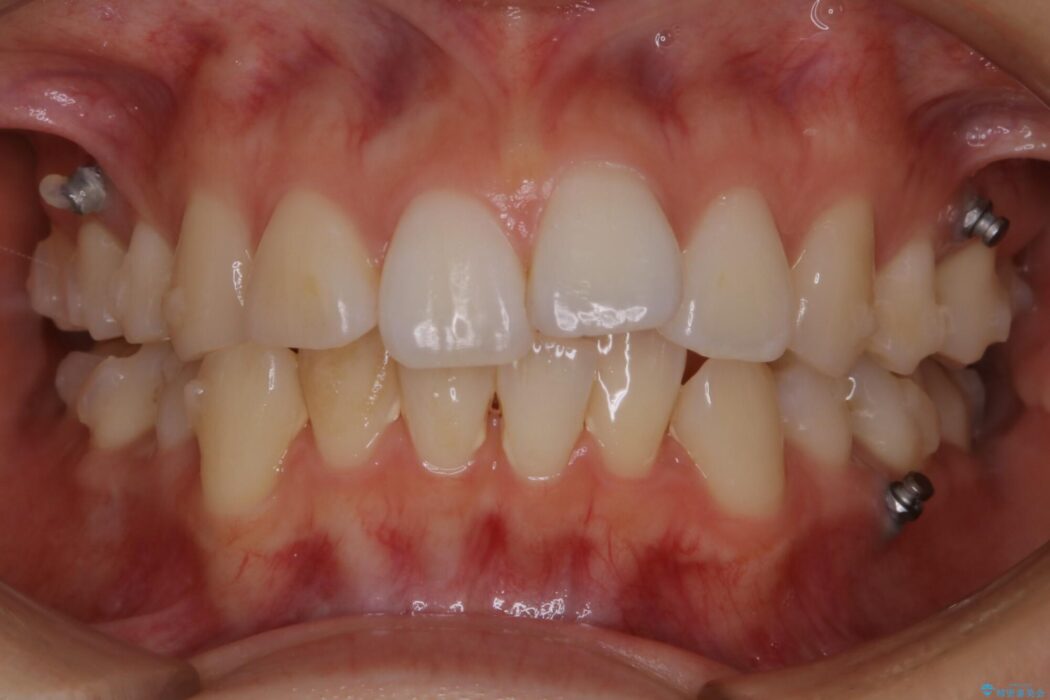

以前治療した抜歯矯正から後戻りをしてしまった歯列のがたつきを再矯正したいとのことで来院されました。

元々中学生から高校生にかけてワイヤー装置を用いた矯正治療をされた患者様でした。

大人になるにつれてライフスタイルの変化が生じ、歯が元の位置に戻らないように保定するためのリテーナーを継続使用することが難しくなったことから、歯列にがたつきが目立つようになったのでもう一度矯正治療をしたいとのご希望でした。

既に上下左右の4番目の歯が抜歯されているため、今回のケースでは非抜歯による歯の移動のみで矯正をしなければならず、難易度が高いものになりました。

後戻りしていた歯列もきれいに整い患者様にはご満足いただけました。